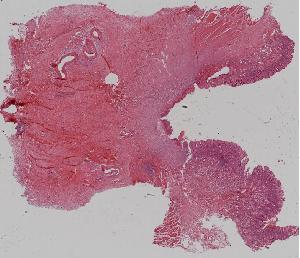

8. Granulation tissue

低倍视野